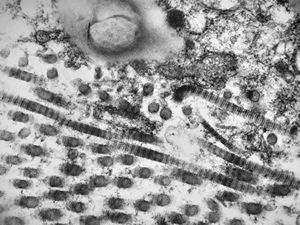

F, 39y. | collagenous and elastin fibers from corium

F, 39y. | collagenous and elastin fibers from corium